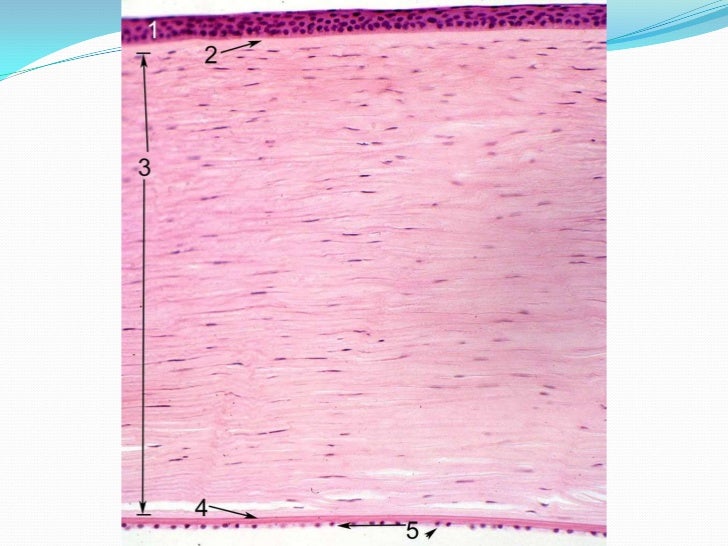

GLOBO OCULAR HISTOLOGIA

GLOBO OCULAR HISTOLOGIA What Is A Tunica Fibrosa The human eye is an organ that reacts to light and allows vision. The eye is the specialized organ of sight which has three principal layers, the fibrous. Tunica is a term for a layer, coat, or covering in biology, especially in botany and zoology. Learn about the different types and functions of tunica. 1 the eyeball (bulbus oculi) 1.1. What Is A Tunica Fibrosa.